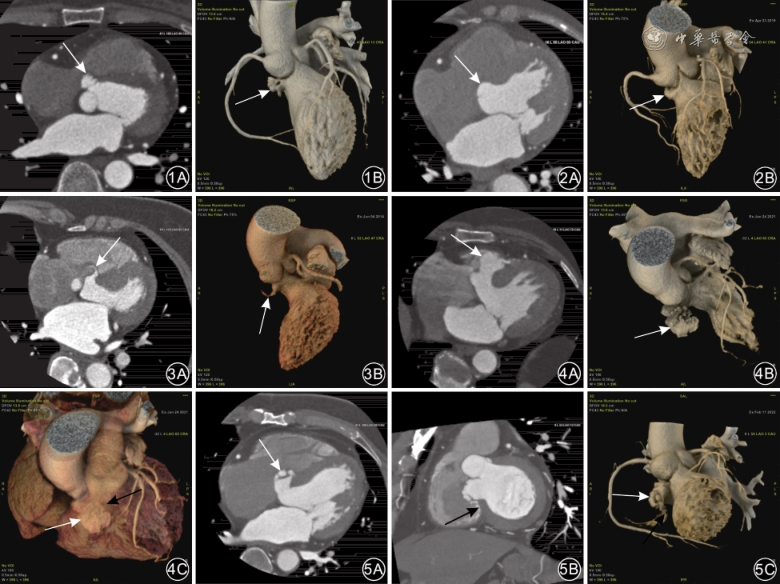

50例IVMSA的形态可分为多叶状、半球形和隧道样3种类型。(1)多叶状47例,表现为形态呈多分叶状,分叶可大小不均,此类型最多见(图1)。(2)半球形2例,表现为表面较光滑,瘤颈直径大于瘤体长径(图2)。(3)隧道样1例,表现为弯曲长条形瘤腔,游离于右心室内,瘤体长径超过瘤颈直径4倍(图3)。多叶状的数量显著高于其他2种形态的数量。

IVMSA膨出方向分为膨向右室流入道和膨向右室流出道两种情况。其中49例膨向右室流入道,1例膨向右室流出道(图4)。

1例室间隔缺损修补患者术后形成的膨出瘤,瘤壁局部显示不连续,可见对比剂分流征象(图5),提示膨出瘤瘤壁破裂,其余49例IVMSA均未检出瘤壁破裂情况。